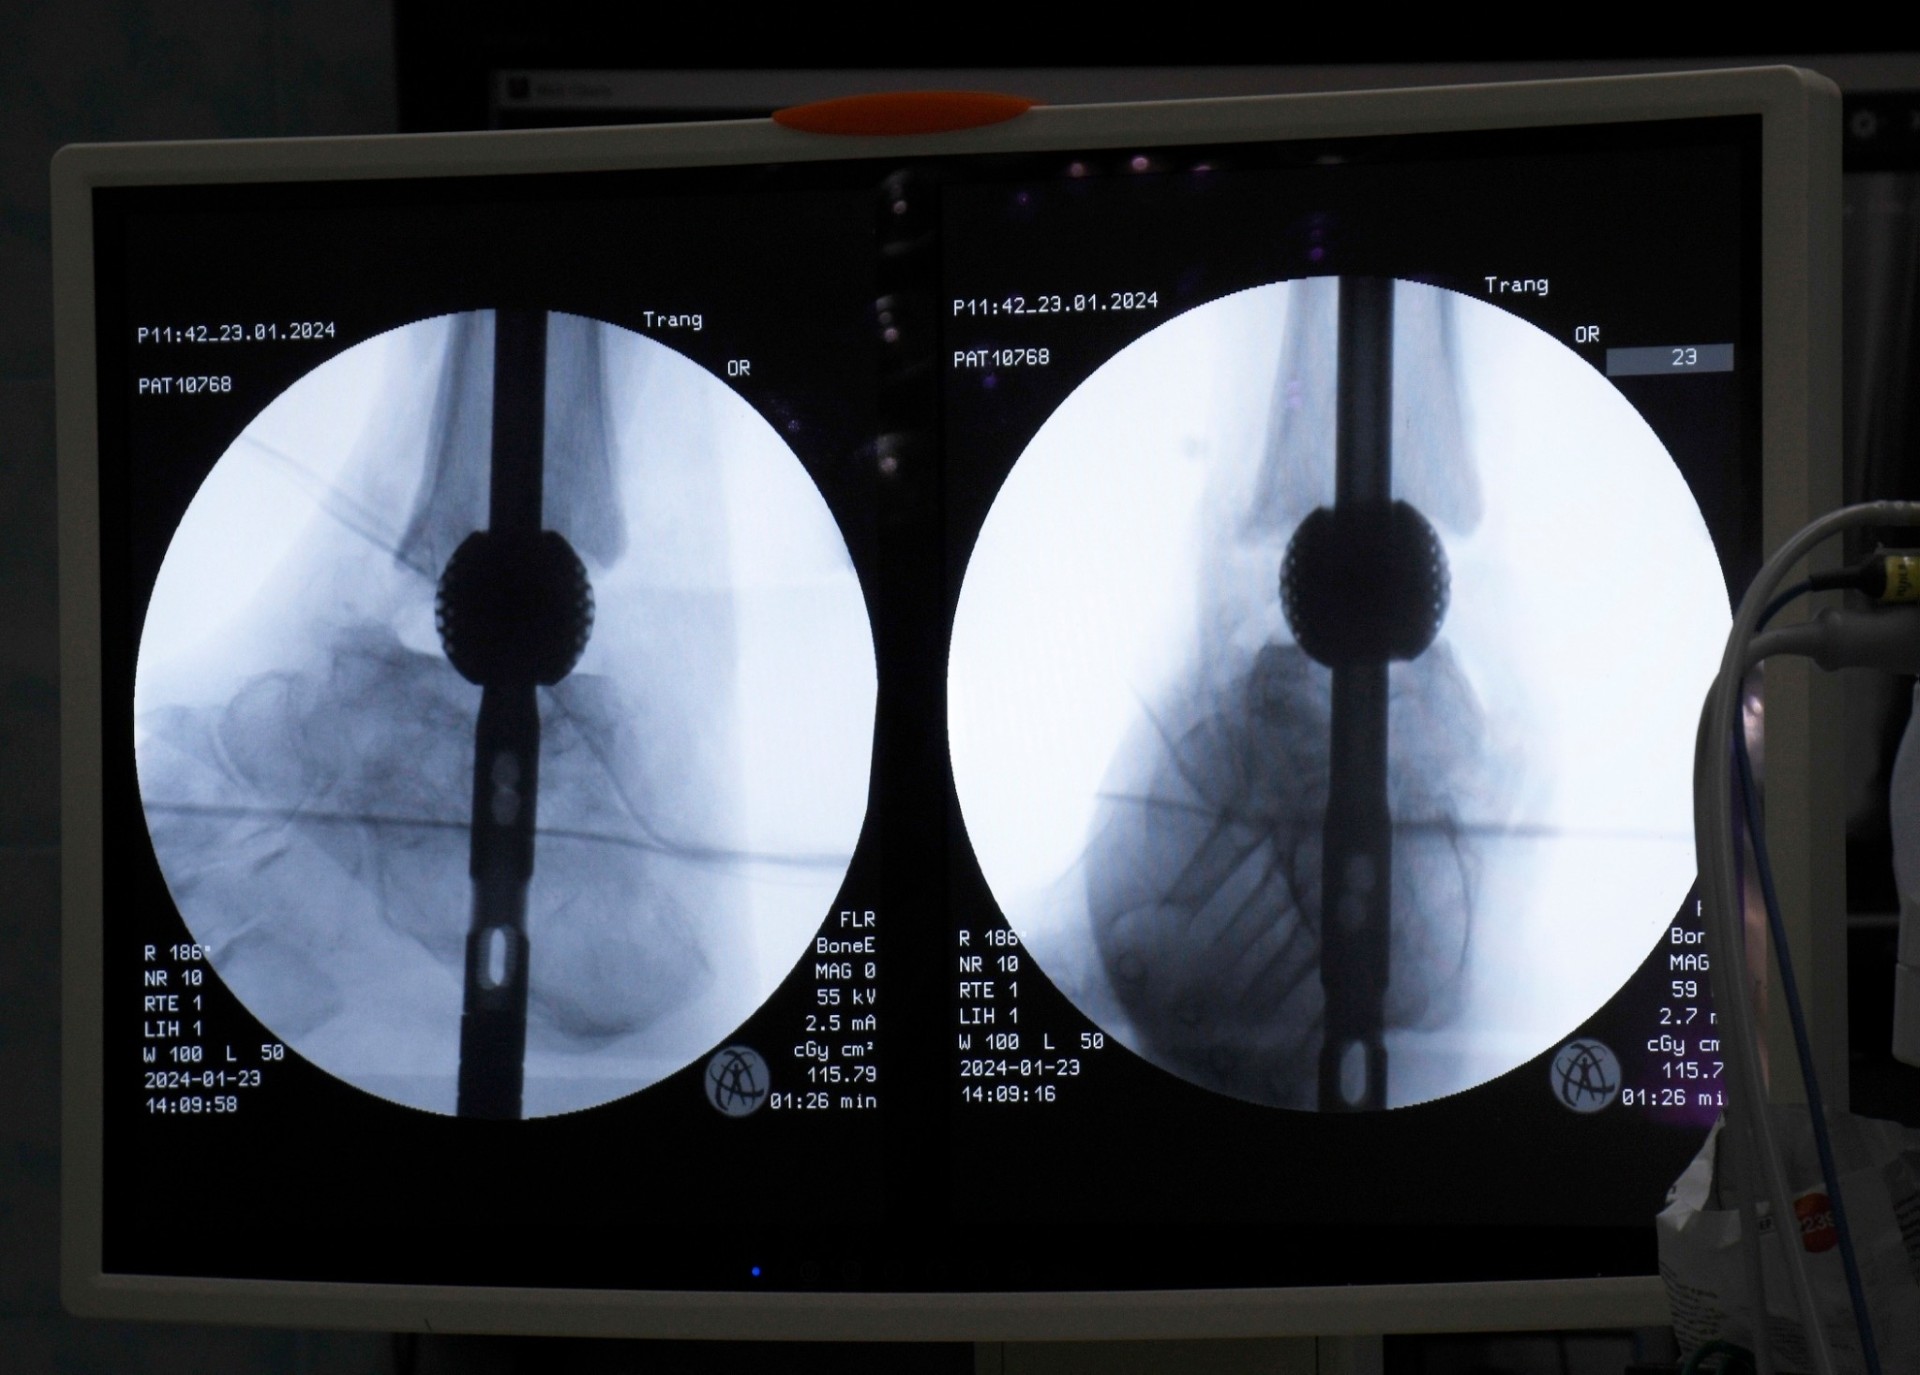

รศ.ดร.พชรพิชญ์ กล่าวว่า เทคโนโลยีนี้โดดเด่นด้วยการออกแบบเฉพาะบุคคล ความสามารถในการผสานร่วมกับกระดูกตามธรรมชาติได้ดี และลดความเสี่ยงของการติดเชื้อซ้ำได้อย่างมีนัยสำคัญ ซึ่งนำไปสู่คุณภาพชีวิตที่ดีขึ้นของผู้ป่วย ผลงานวิจัยนี้สะท้อนให้เห็นถึงความสำเร็จทางการแพทย์ในเคสที่มีความท้าทายสูง อาทิ ผู้ป่วยข้อเท้าเสื่อมที่มีภาวะกระดูกติดเชื้อจากโรงพยาบาลตรัง และผู้ป่วยกระดูกหักที่กระดูกไม่ติดกันจากอุบัติเหตุในโรงพยาบาลสงขลานครินทร์ ซึ่งทั้งหมดประสบความสำเร็จในการรักษาผู้ป่วยให้สามารถกลับมาเดินได้ตามปกติ แสดงให้เห็นว่าวัสดุหรืออุปกรณ์ที่พัฒนาขึ้นนี้มีความสามารถในการปรับใช้กับกระดูกได้หลากหลายชิ้นทั่วร่างกาย ตอกย้ำถึงความอเนกประสงค์ของเทคโนโลยี

รศ.ดร.พชรพิชญ์ เล่าว่า จากแนวคิดที่เริ่มต้นเป็นเพียงงานวิจัยขั้นพื้นฐานเมื่อกว่า 2 ปีก่อน ที่ทีมวิจัยเชื่อว่าน่าจะสามารถต่อยอดไปสู่อุปกรณ์ทางการแพทย์ได้ ปัจจุบันได้พัฒนาและนำไปใช้จริงกับผู้ป่วยแล้ว ทั้งจากการติดต่อโดยตรงของผู้ป่วยและจากการส่งต่อโดยแพทย์เจ้าของไข้ ตัวอย่างเช่น กลุ่มผู้ป่วยข้อเท้าเสื่อมที่มีภาวะกระดูกติดเชื้อจากโรงพยาบาลตรังจำนวน 7 ราย ซึ่งนำเทคโนโลยีโครงสร้างวัสดุพรุนจาก 3D Printing มาช่วยแพทย์ในการผ่าตัดรักษา ผลลัพธ์พบว่า ภายใน 1 ปี ผู้ป่วยสามารถกลับมาเดินได้ตามปกติทุกคน จากเดิมที่ผู้ป่วยบางรายมีความเสี่ยงต้องถูกตัดขาและไม่สามารถใช้ชีวิตได้อย่างปกติ นวัตกรรมนี้ช่วยเปลี่ยนคุณภาพชีวิตของพวกเขาไปอย่างสิ้นเชิง ความสำเร็จดังกล่าวยังนำไปสู่การยื่นจดสิทธิบัตรในประเทศสหรัฐอเมริกา ร่วมกับ นายแพทย์จรวด จำปา อาจารย์แพทย์โรงพยาบาลตรัง เพื่อขยายการใช้งานอุปกรณ์สู่ระดับนานาชาติ โดยเฉพาะอย่างยิ่งกับโรคเบาหวานที่ถือเป็นปัญหาสาธารณสุขสำคัญทั่วโลก